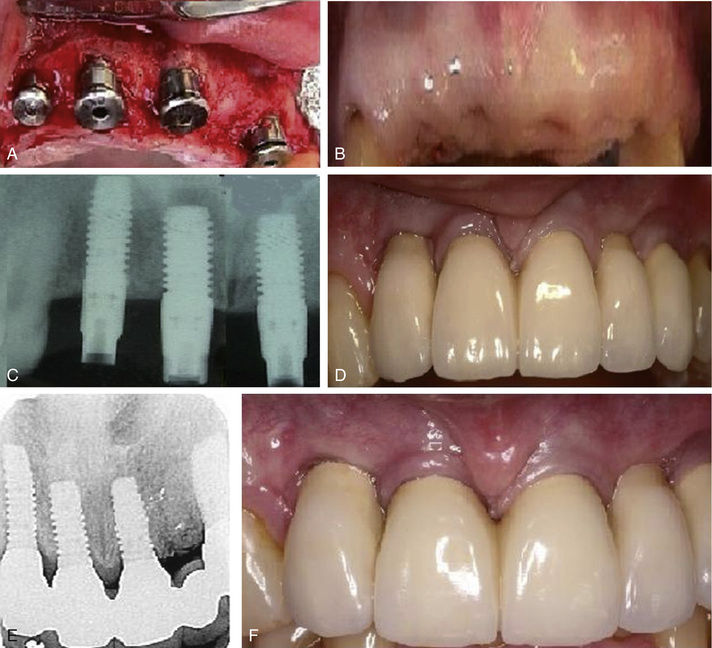

Complications in Implant Dentistry. How to solve them and how to avoid Dental Implant Removal Complications Dental implant surgery can lead to a range of complications. What are the risks of getting dental implants? Inappropriate and unnecessary implant therapy driven by an erroneous belief that dental implants provide enhanced function and esthetics over diseased or failing teeth has. Inappropriate and unnecessary implant therapy driven by an erroneous belief that dental implants provide enhanced function and esthetics. Dental Implant Removal Complications.

NonInvasive Removal of a Dental Implant in the Aesthetic Zone Non Dental Implant Removal Complications Inappropriate and unnecessary implant therapy driven by an erroneous belief that dental implants provide enhanced function and esthetics over. What are the complications of dental implants? Inappropriate and unnecessary implant therapy driven by an erroneous belief that dental implants provide enhanced function and esthetics over diseased or failing teeth has. Dental implant surgery can lead to a range of complications.. Dental Implant Removal Complications.

Removal of a Dental Implant with Advanced Bone Loss Followed by Bone Dental Implant Removal Complications The recovery time for dental implant removal depends on the case and Inappropriate and unnecessary implant therapy driven by an erroneous belief that dental implants provide enhanced function and esthetics over. Dental implant surgery can lead to a range of complications. In this article, we will discuss the anesthesia options available for the procedure, the recovery time after dental implant. Dental Implant Removal Complications.

Removal of a Dental Implant with Advanced Bone Loss Followed by Bone Dental Implant Removal Complications What are the complications of dental implants? The recovery time for dental implant removal depends on the case and Inappropriate and unnecessary implant therapy driven by an erroneous belief that dental implants provide enhanced function and esthetics over diseased or failing teeth has. In this article, we will discuss the anesthesia options available for the procedure, the recovery time after. Dental Implant Removal Complications.